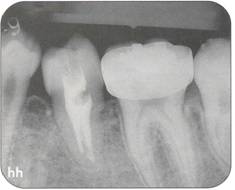

Fi 545e45f g 5-4f Extracted second molar, which will be discarded. Fi 545e45f g Extracted donor tooth. The amount of periodontalligament is adequate. Transplantation was performed 6 weeks after extraction of the tooth from the recipient site. Fi 545e45f g 5-4h View of the donor site and preparation of the recipient site. |

Fi 545e45f g 5-4i After the gingival flap has been sutured and the donor tooth has been splinted. The distal aspect of the donor tooth is closed as tightly as possible. Fi 545e45f g 5-4j After transplantation. Fi 545e45f g 5-4k Two weeks after trans plantation |

Fi 545e45f g 5-41 Six weeks after transplantation. The root canals have been cleaned, shaped, and filled with calcium hydroxide. Fi 545e45f g 5-4m Three months after transplantation. The radiograph was taken after removing the splint. Fi 545e45f g 5-4n Seven months after transplantation. |

Fi 545e45f g 5-40 Seven months after transplantation. Mesial migration of the donor tooth and regeneration of alveolar bone can be observed. Fi 545e45f g 5-4p One year after transplantation. Fi 545e45f g 5-4q Two years after transplantation. |